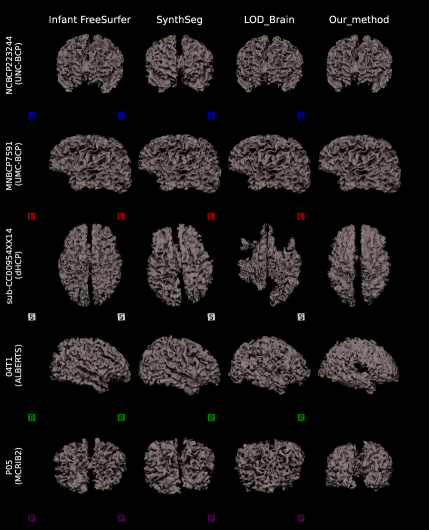

5.2 Qualitative comparisons on raw infant data

To provide a clear visual assessment of segmentation performance, we present a diverse set of qualitative results obtained using different methods. Figs 4 and 5 illustrate a side-by-side comparison between the competing approaches and the silver-standard ground truth generated by Infant FreeSurfer. Specifically, we highlight the 30 most discordant MRI volumes, identified as those exhibiting the highest variance in DICE scores across the evaluated methods when compared to Infant FreeSurfer segmentations. By focusing on these challenging cases, we enhance the visibility of key differences in anatomical structure delineation, allowing for a more insightful comparison of method effectiveness.

This visualization strategy ensures that performance disparities between compared approaches are clearly distinguishable, providing an intuitive and informative perspective on the strengths and limitations of each method, including our proposed solution.

5.2.1 Surface analysis on raw infant data

We perform a surface-based analysis using all methods, that are Infant FreeSurfer, SynthSeg, LOD-Brain, and LODi, to evaluate segmentation performance across different anatomical surfaces. Specifically, we analyze the surfaces of the inner gray matter (Fig.7(a)), and of the outer gray matter (Fig.7(b)).

This analysis is conducted on five MRI volumes, each selected from a different dataset (BCP-UMN-site, BCP-UNC-site, dHCP, ALBERTS, and MCRIB2), based on the scan exhibiting the highest variance in Dice scores across methods. Similar to the qualitative comparison, this selection strategy emphasizes cases where segmentation results show the greatest discrepancies.

By visualizing these 3D surface representations, generated using nii2mesh, we provide a more detailed assessment of LODi?s ability to accurately capture anatomical brain structures. Notably, this approach also highlights the smoothness of the resulting segmentations, and facilitates a direct comparison with benchmark methods, offering deeper insights into segmentation performance across different surfaces.